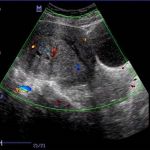

子宫腺肌症,子宫肌瘤,子宫出血等良性疾病,用切除子宫来治疗弊大于利,安太医院签约去病保宫宫腹腔镜手术。